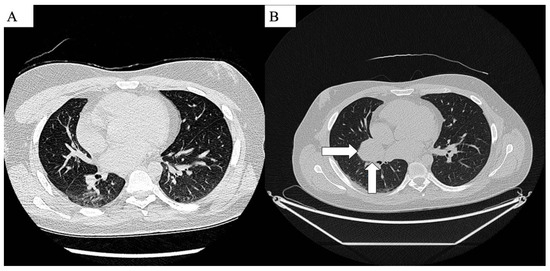

| 13 | Presented case | M/24 | Dyspnea, heartburn, intermittent tachycardia, right shoulder pain, expectoration of white sputum | Left lateral retroperitoneal region | 22 × 13 | Surgery, Trametinib treatment | NR |